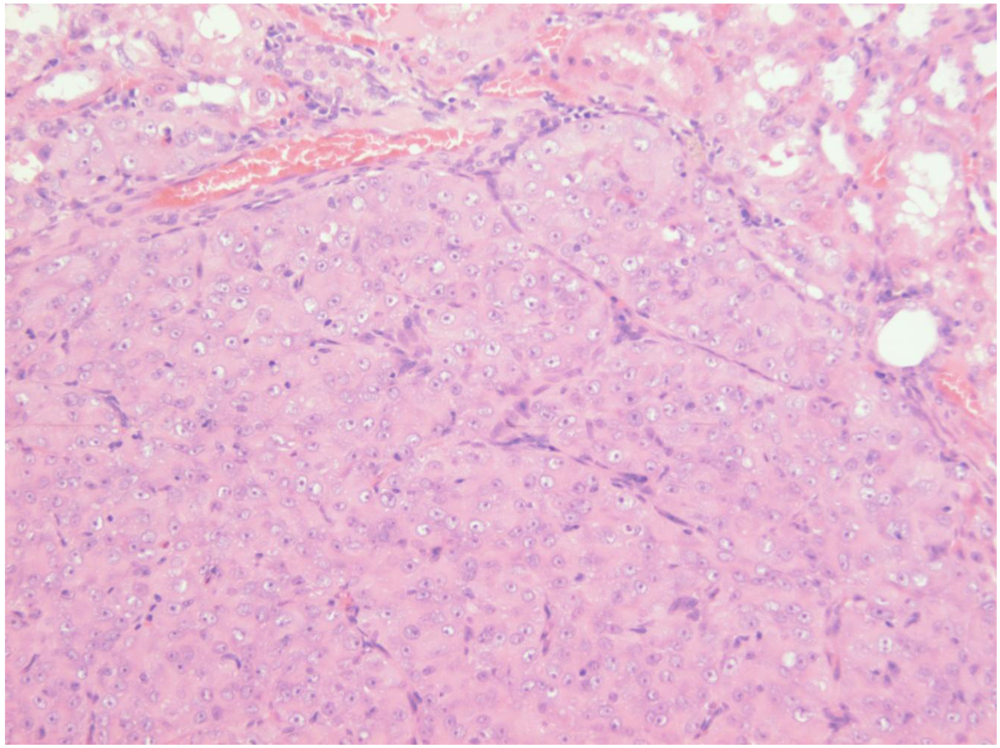

Finally, the 5th animal was losing weight (Figure 2) at 2 years 10 months of age and was euthanised; the left kidney was cystic (typical of ageing rats) but the right kidney bore a large tumour that distorted the caudal pole (Figure 7A, total tumourous kidney weight 10 g). The tumour histopathology was typical of OTA-induced renal carcinoma (Figure 7B). Repeated attempts to measure DNA ploidy distribution failed for this tumour; nuclei were very large, with cleared centres after staining, and the scanning software could not recognise them. Thus 40% of these rats developed renal tumours and none became apparent until 2 years after the experiment commenced.

Figure 7.

Male rat given the OTA regimen only. A, renal carcinoma causing organ distortion at the caudal pole; note renal papilla still entire. B, photomicrograph of H and E stained section of renal carcinoma; note disorganisation of tissue, frequent enlarged nuclei with prominent nucleoli and one very large nucleus.